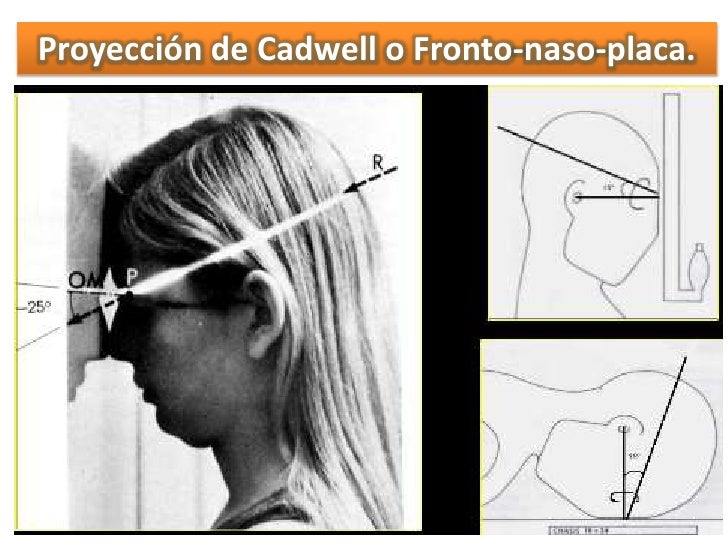

Proyección de Caldwell. La radiografía de Caldwell ( Caldwell's view en inglés) o también llamada radiografía postero-anterior (PA) de senos paranasales, es una proyección radiológica específica para la visualización de los senos frontales y etmoidales. 1 Los pacientes con sospecha de sinusitis frontal (cefalea frontal predominante.

Proyección de Cadwell. Diccionario médico. Proyección radiológica para el estudio del macizo facial, también denominada frontonaso placa, de utilidad en la valoración de los senos frontoetmoidales. QUIERO ESTAR INFORMADO. La información proporcionada en este Diccionario Médico de la Clínica Universidad de Navarra tiene como objetivo.

Citation, DOI, disclosures and article data. The Caldwell view is a caudally angled radiograph, with its posteroanterior projection allowing for minimal radiation to the orbits. This view may be used in imaging of the skull or facial bones depending on the clinical indications.

RX1 CADWELL. La radiografía de Caldwell o también llamada radiografía postero-anterior (PA) de senos paranasales, es una proyección radiológica específica para la visualización de los senos frontales y etmoidales. Los pacientes con sospecha de sinusitis frontal (cefalea frontal predominante) deben ser dirigidamente estudiados mediante.

Proyección de Caldwell Wikiwand

grupos de senos. Proyección PA axial (Método Cadwell): Senos frontales y etmoidales anteriores. Proyección de Waters (Parietoacantial): con boca cerrada: Senos maxilares Proyección de Waters (Parietoacantial) con boca abierta: Senos maxilares y esfenoidales. Proyección Submentovertical: Senos etmoidal y esfenoidal. Centraje: Línea.

Proyección de Caldwell: proyección AP de los senos paranasales en flexión de la cabeza, placa entre. Proyeccion lateral: imagen del plano sagital del paciente. 3. Indicación. -Trauma facial. -Actualmente la radiografía simple de cavidades paranasales no se recomienda para el estudio de sinusitis aguda, ya que su diagnóstico es clínico. 4.

APLICACIONES RADIOLÓGICAS EN LAS CIENCIAS FORENSES Proyección CADWELL ( Para visualizar senos